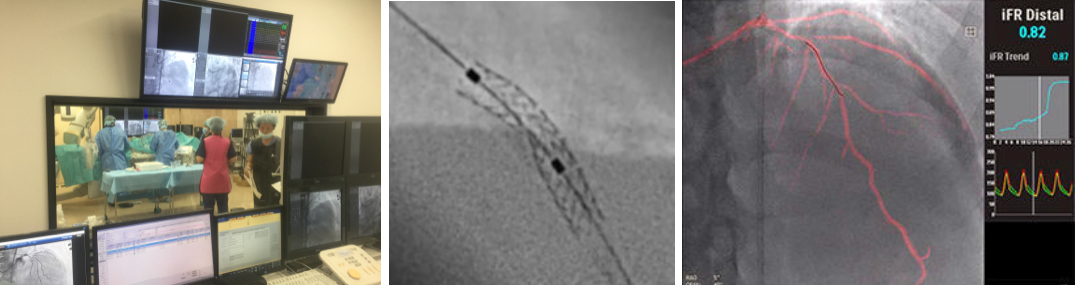

カテーテル検査・治療

カテーテル室では、冠動脈ステント治療をはじめ下肢動脈やシャント血管の治療、ペースメーカー植え込み治療、心臓電気生理検査およびカテーテルアブレーション治療などが行われます。

ハイブリッドオペ室(Hybrid OR)

オペ室とカテーテル室の両方の機能を持つハイブリッドオペ室では、大動脈ステントグラフト術やペースメーカーなどの植込み型心臓電気デバイスの植え込み術などが行われます。